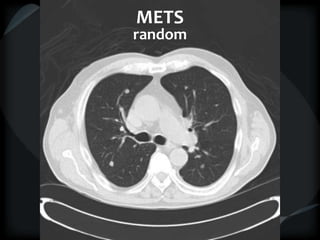

METS

random

 Nodular – random

● SP, septal, non-axial

● Mets, miliary